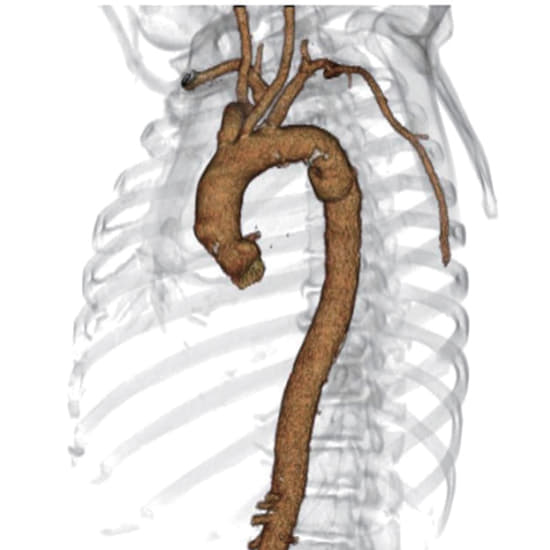

遠位弓部大動脈瘤に対するゴア

®

TAG

コンフォーマブル 胸部大動脈ステントグラフト アクティブコントロールシステムの有用性およびKEY POINT

さらに詳しく